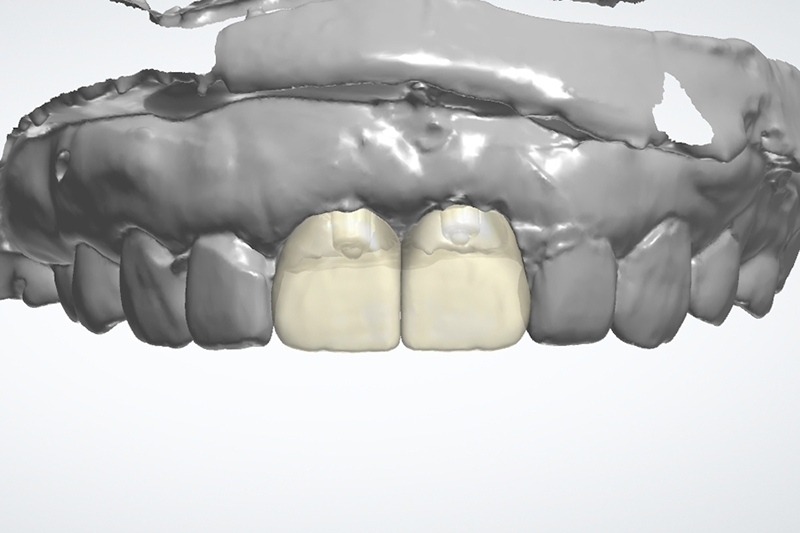

同時數位口內掃描影像取模

利用數位口掃全瓷冠數位設計檔

客製化金屬支台齒